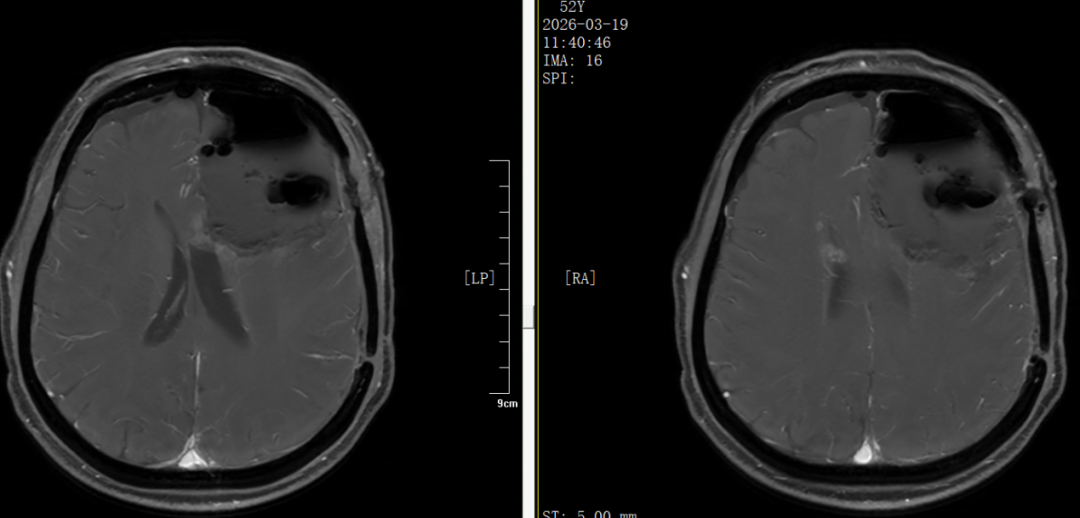

术后48小时复查MRI提示 肿瘤切除范围满意,无异常出血及梗塞